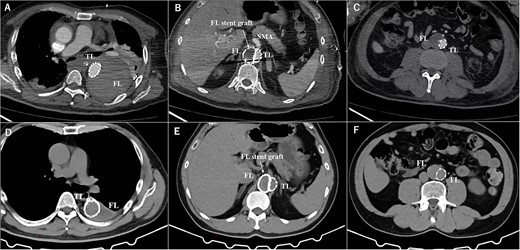

A 57-year-old man, with a history of acute Stanford type B aortic dissection from the descending thoracic aorta extending to the right common iliac artery (CIA), had been treated conservatively for 10 years. He admitted to the hospital with chief complaint of sudden-onset back pain. The contrast-enhanced computed tomography (CT) imaging revealed CTBAD extending from the distal aortic arch to the right CIA, with a rupture in the thoracic aorta. The diameter of TAAA was 71 mm. The primary entry was located at the descending aorta close to the subclavian artery. Multiple intimal tears were present at the descending aorta, as well as at the level of superior mesenteric artery (SMA) and renal artery (RA). The right RA was originated from the FL (Fig. 1A). Considering the invasiveness of conventional aortic replacement under left thoracotomy, we decided to perform endovascular repair.

The postoperative contrasted computed tomography at thoracic level (A), at SMA level (B), at abdominal level (C). The computed tomography three years after the operation at thoracic level (D), at SMA level (E), at abdominal level (F). TL: true lumen FL: false lumen RA: renal artery CA: celiac artery SMA: superior mesenteric artery CIA: common iliac artery.